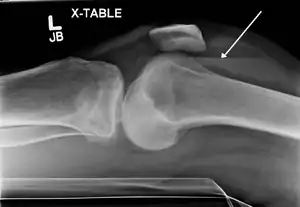

Lipohemarthrosis (blood and fat in the joint space) seen in a person with a subtle tibial plateau fracture. The arrow indicates a fluid level between the upper fat component and the lower blood component.